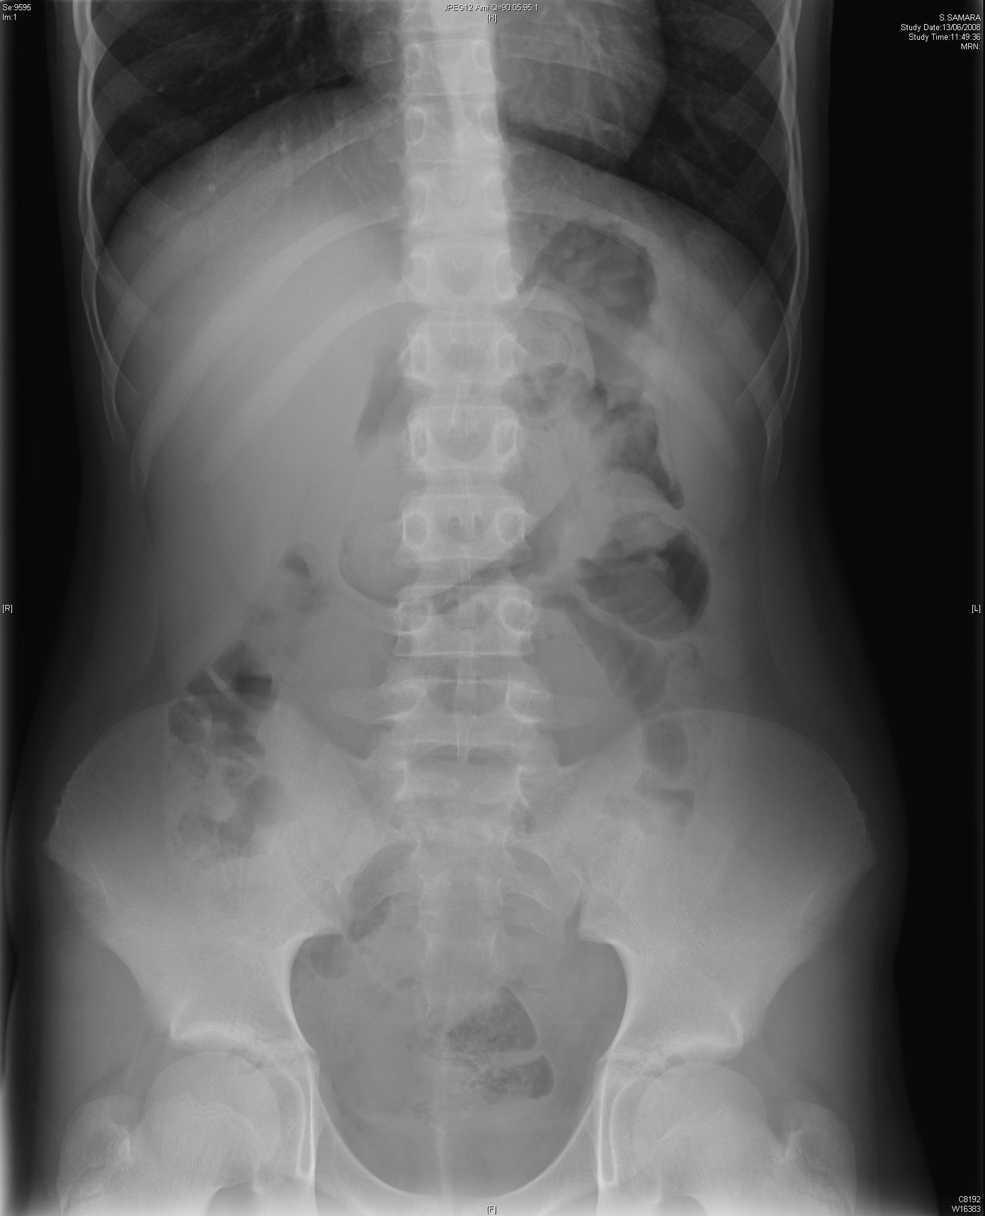

Se inicia tratamiento sintomático. Ante la persistencia de los vómitos, se realiza radiografía abdominal, en la que se visualiza el estómago con contenido y distribución normal de gas intestinal. En la ecografía abdominal se visualiza (fig. 1) el estómago distendido, con una imagen hiperecogénica de 6 cm de longitud en el antro, ovalada y que impide el vaciamiento gástrico (posible cuerpo extraño). Se realiza una interconsulta a cirugía y la paciente ingresa. Durante el ingreso se realiza tránsito digestivo (fig. 2) que confirma la presencia de una masa densa en el estómago que ocupa toda la cavidad gástrica y deja pasar contraste. Se interviene quirúrgicamente a la paciente para la extracción del tricobezoar mediante gastrostomía. Durante el ingreso inició una evaluación psicológica.

Figura 1. Ecografía de abdomen: imagen hiperecogénica ovalada en estómago de 6 cm de longitud con sombra acústica posterior.

Los síntomas del tricobezoar son dolor abdominal, náuseas, vómitos, anorexia, saciedad temprana, debilidad, pérdida de peso y masa abdominal. Sin diagnóstico puede dar lugar a complicaciones serias: obstrucción intestinal, perforación, pancreatitis, invaginación, hemorragia intestinal por gastritis, ictericia obstructiva, enteropatía pierdeproteínas y anemia. Puede haber alteración del patrón de deposiciones1,3,4. A menudo pasa desapercibido porque no se menciona la historia de tricofagia. El diagnóstico se basa en la clínica y en las pruebas de imagen. La radiografía abdominal no es diagnóstica (masa heterogénea en el estómago que puede confundirse con un estómago lleno de comida), y se debe confirmar con tránsito digestivo (el contraste identifica una masa intraluminal y libre). La ecografía (imagen hiperecogénica con sombra acústica) y la tomografía computarizada (la imagen más característica es una masa intraluminal heterogénea con patrón de aire moteado, y es más sensible para definir la localización) son las pruebas más fiables5–7. Mediante la laparoscopia se visualiza y ésta puede ser eficaz en la extracción, pero a menudo requiere laparoscopia o laparotomía2,3,8. Se recomienda tratamiento psiquiátrico para prevenir recidivas.